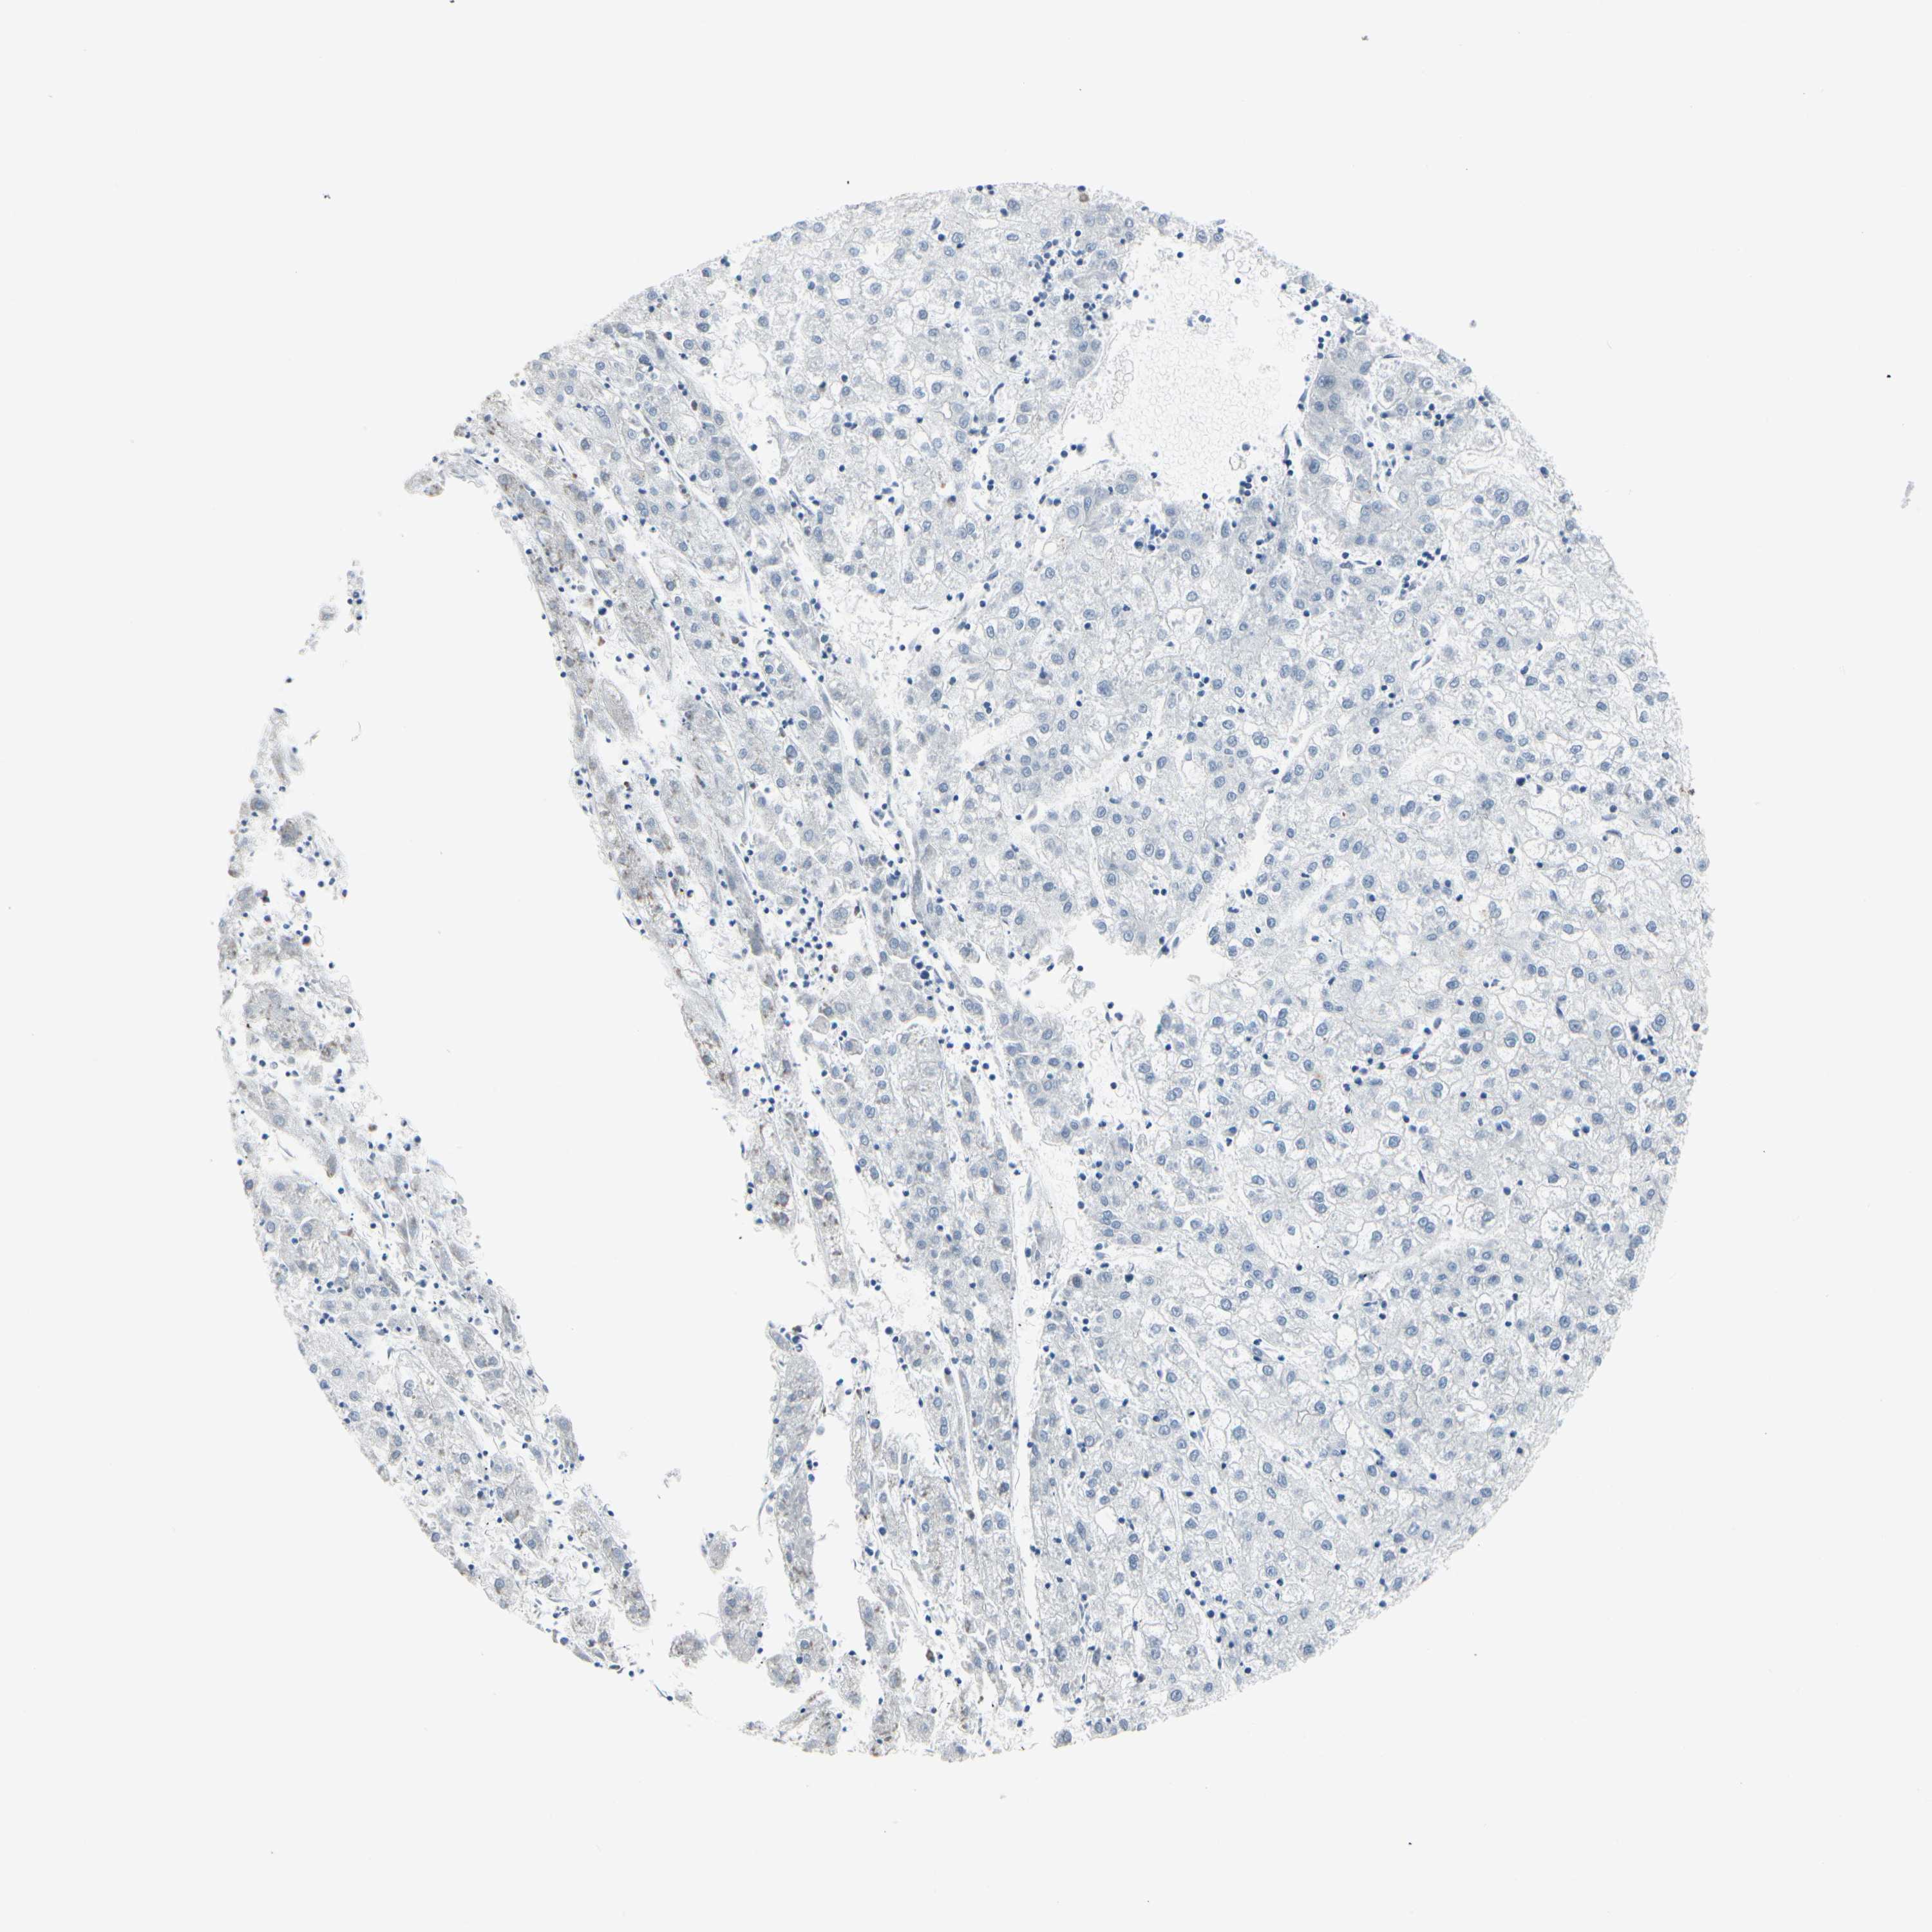

LIVER CANCER - Protein expressioni

A mouse-over function shows sample information and annotation data. Click on an image to view it in a full screen mode. Samples can be filtered based on level of antibody staining by selecting one or several of the following categories: high, medium, low and not detected. The assay and annotation is described here.

Note that samples used for immunohistochemistry by the Human Protein Atlas do not correspond to samples in the TCGA dataset.

Antibody stainingi

Antibody staining in the annotated cell types in the current human tissue is reported as not detected, low, medium, or high, based on conventional immunohistochemistry profiling in selected tissues. This score is based on the combination of the staining intensity and fraction of stained cells.

Each image is clickable and will lead to virtual microscopy that enables deeper exploration of all samples and also displays staining intensity scores, fraction scores and subcellular localization as well as patient and tissue information for each sample.

Antibody HPA008246

Antibody CAB009396

Staining

High

Medium

Low

Not detected

Intensity

Strong

Moderate

Weak

Negative

Quantity

>75%

75%-25%

<25%

None

Location

Nuclear

Cytoplasmic/membranous

Cytoplasmic/membranous,nuclear

Cholangiocarcinoma

Carcinoma, Hepatocellular, NOS